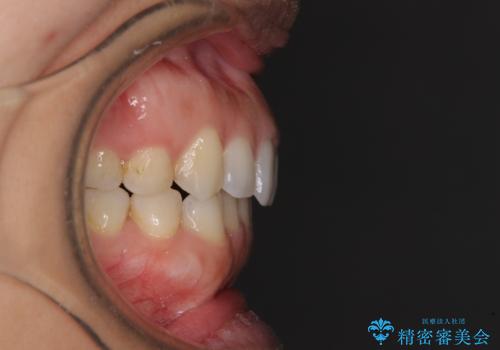

受け口傾向の前歯 すきっ歯の改善

- 前歯の隙間と口元の突出感を気にして来院された患者様です。

嚥下時に舌を突出させる癖があり、成長期に下顎が有意に成長し、歯と歯の間に隙間ができてしまいました。

舌の癖を改善し、インビザラインにて治療を行うこととしました。

舌癖を改善したことで、隙間や突出感を改善することができました。

隙間は後戻りしやすいため、舌側を細いワイヤーで固定することとしました。